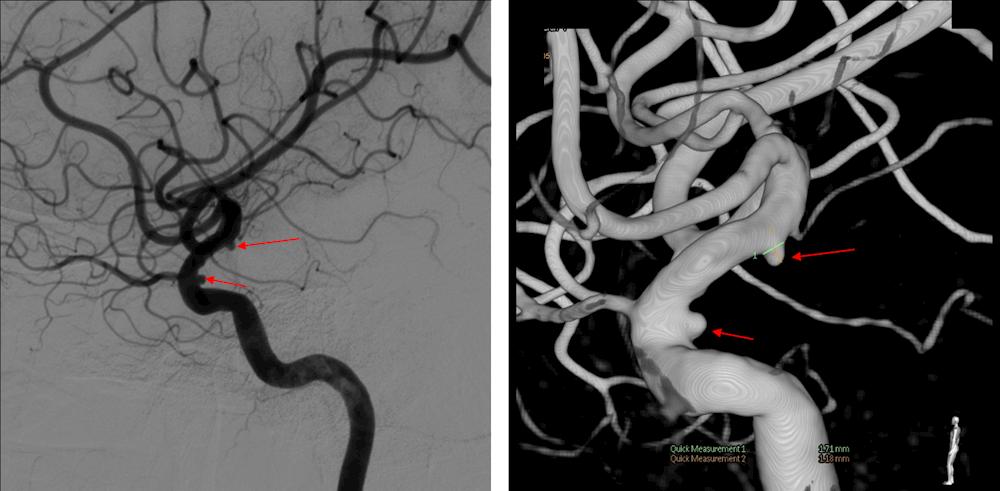

3.神经介入治疗:脑动静脉畸形、脑膜动静脉瘘、脑动脉瘤、脑动脉血栓溶解、脑膜瘤、颈动脉海绵窦瘘等微创介入治疗。

图左:病患右颈内动脉造影显示大脑中动脉有动脉瘤 右侧颈内动脉动脉瘤(红色箭头)

图右:经弹簧圈栓塞后,动脉瘤萎缩消退